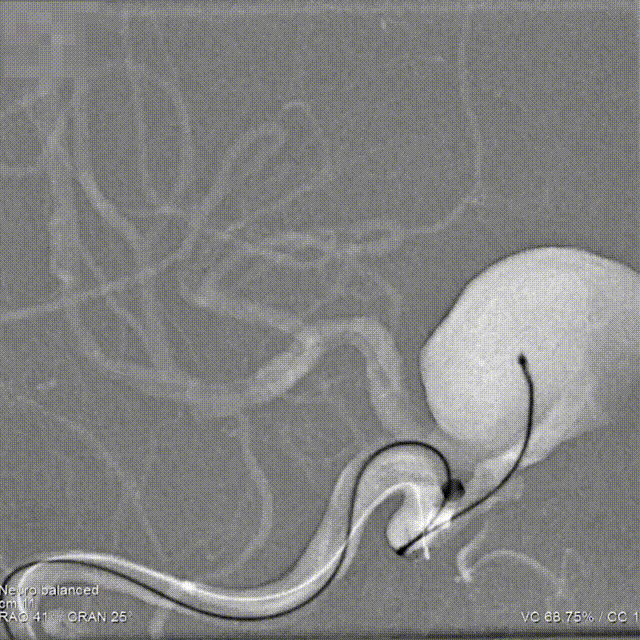

术前造影

术前造影提示:右侧颈内动脉眼动脉段大动脉瘤。

正位造影

侧位造影

3D旋转

术前测量

动脉瘤:长:20.98mm;宽:17.13mm;高:19.08mm;典型颅内动脉大动脉瘤征。

载瘤动脉:瘤颈远端血管径:3.31mm,瘤颈近端血管径:3.80mm,瘤颈远近端长度:约24mm。